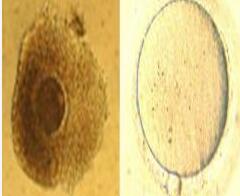

未成熟卵体外成熟技术(In Vitro Maturation,IVM)是试管婴儿领域的一项前沿技术,专门针对一些卵子成熟障碍的不孕患者,特别是那些顽固的多囊卵巢综合症、卵泡发育迟缓、卵巢过度刺激征的患者。

将未成熟的卵母细胞取出,在体外进行培养、受精,然后将胚胎移植到母亲子宫腔内生长。这种技术还可能避免药物和治疗的副作用,减少费用,降低促排卵的风险。